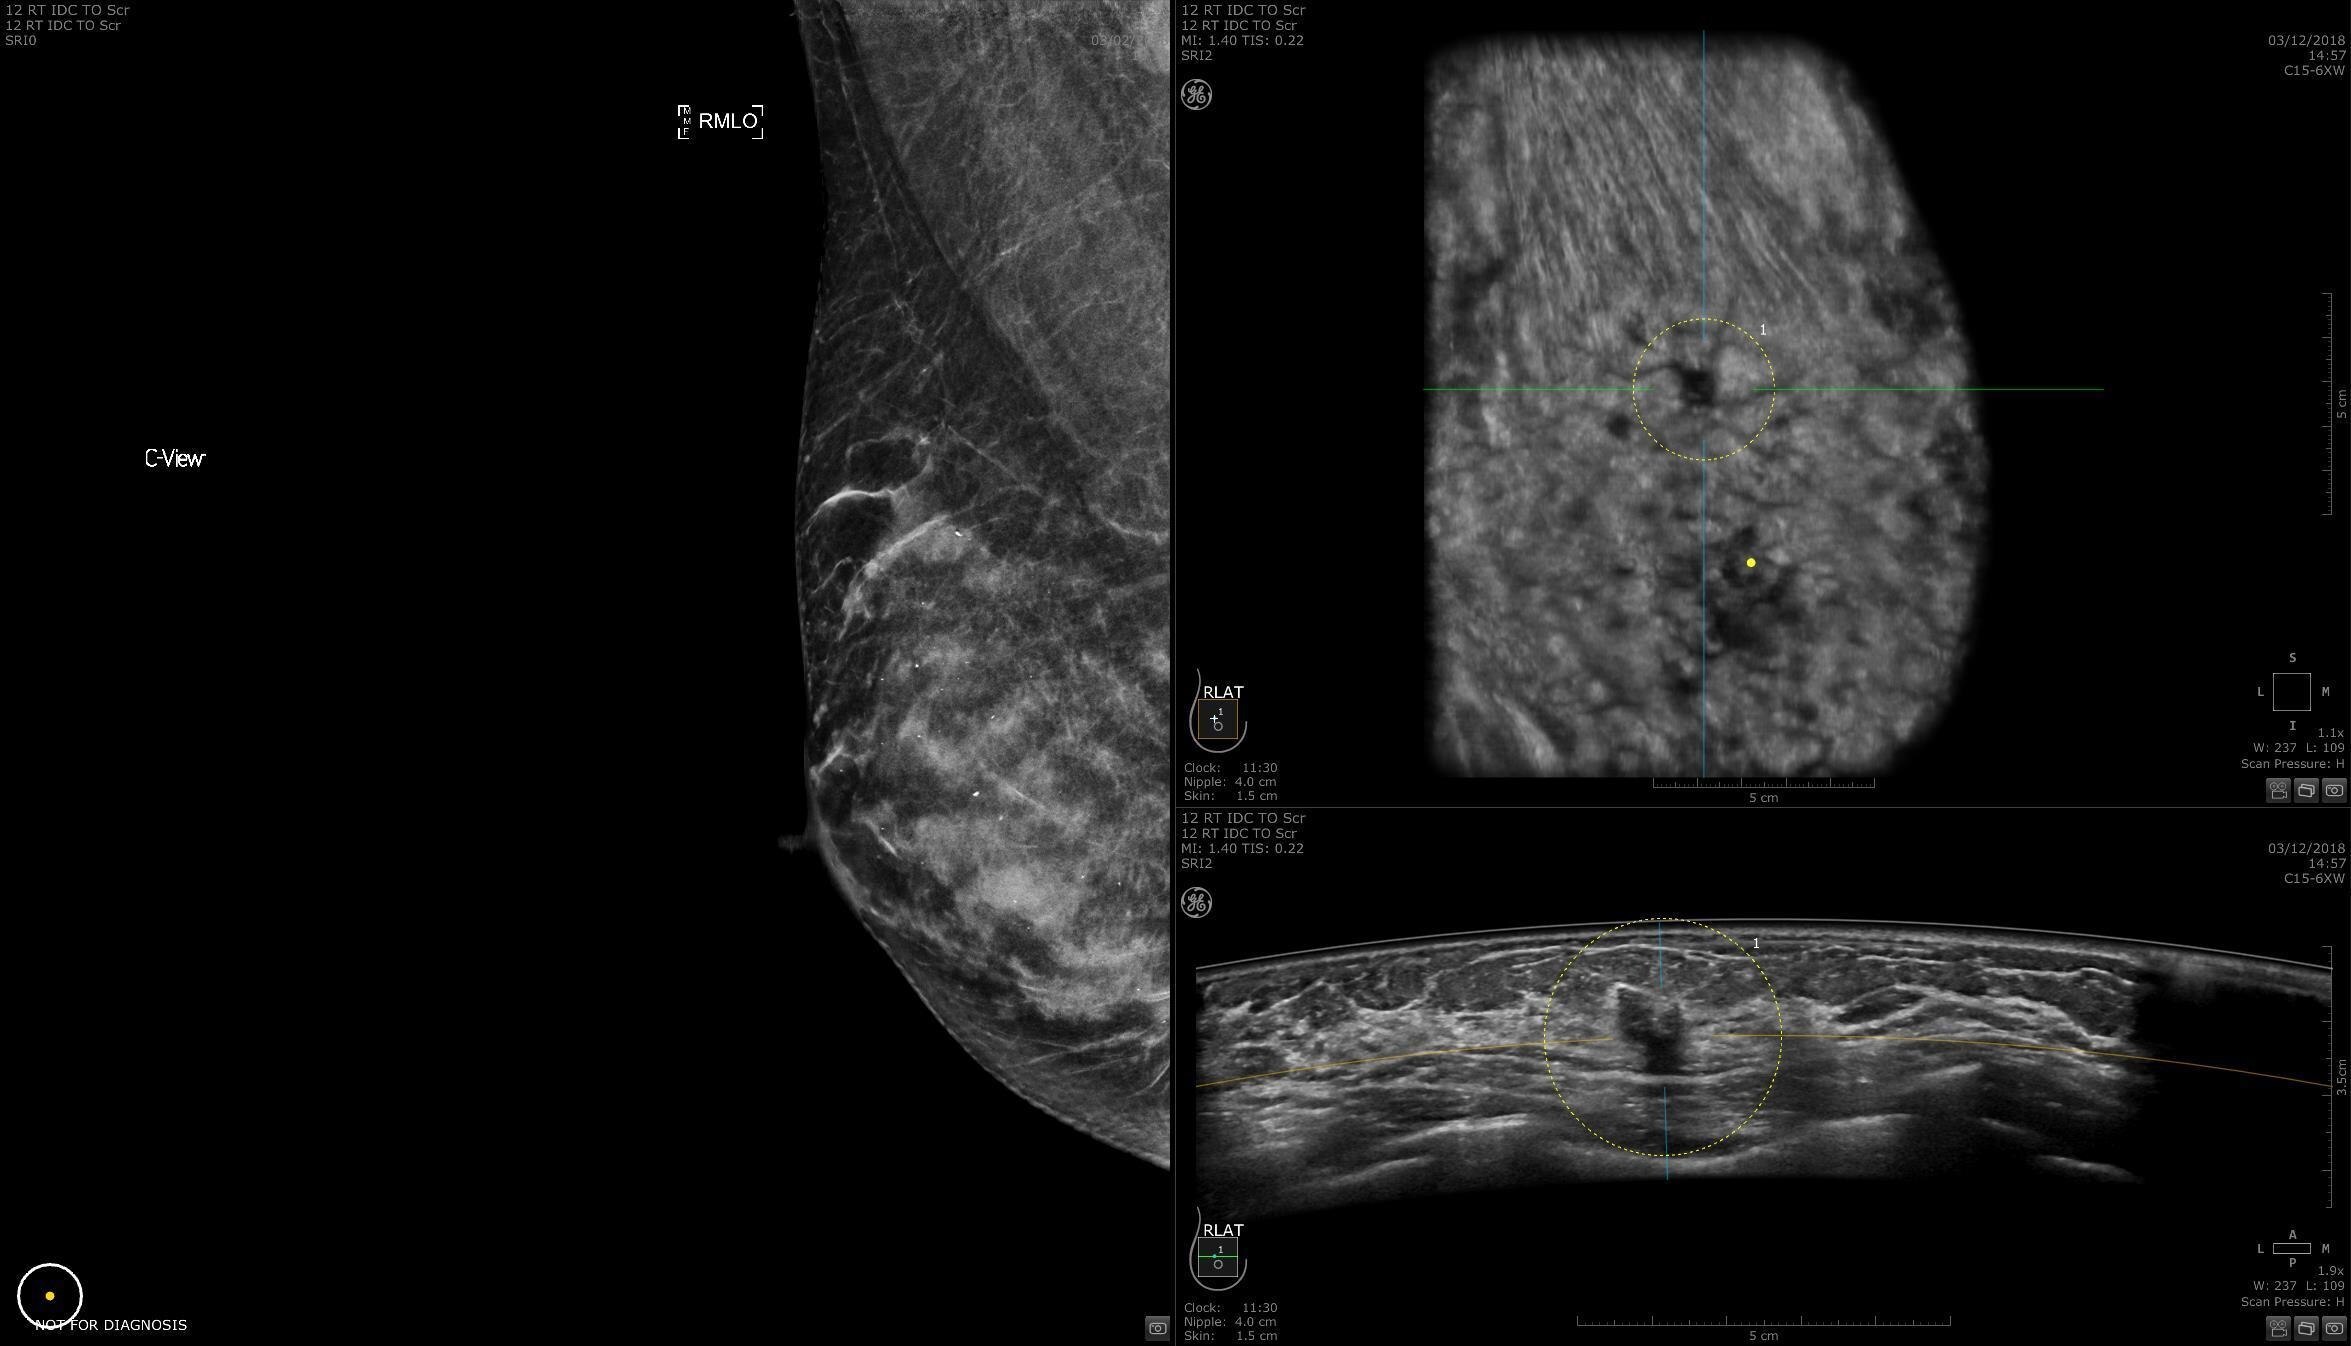

Dense breast tissue and cancer appear white on a mammogram, potentially camouflaging small cancers. Invenia ABUS 2.0, is specifically designed to help clinicians find cancers that may be hidden on mammography1,2.

Lesion characterization for confident staging in dense breasts

Invenia ABUS 2.0 uses the latest ultrasound innovations and AI based solutions to help improve precise diagnosis and elevate clinical confidence.